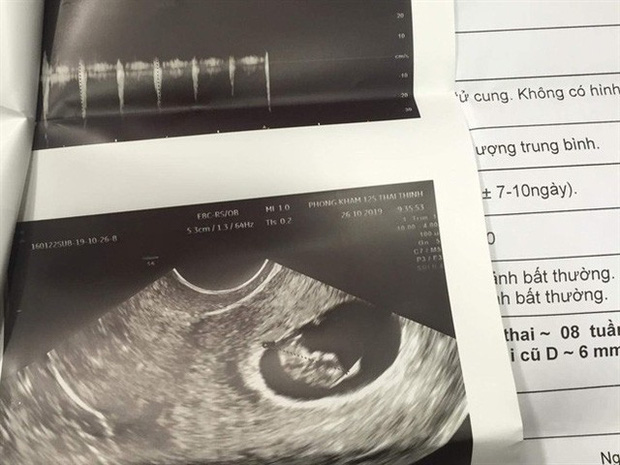

Tuy nhiên, 4 tuần sau ca hút mỡ, khi sức khỏe có vấn đề, chị đi khám thì phát hiện mình đang mang thai tuần thứ 8, kết quả này được 2 cơ sở y tế khác nhau xác nhận.

Chị A và người nhà vô cùng bức xúc chuyện vì sao chị có thai mà các cơ sở (Thẩm mỹ viện Emcas và thẩm mỹ viện S) khi chị thực hiện hút mỡ bụng không biết. Chị N.A cũng lo lắng khi bác sĩ sản khoa tư vấn về khả năng chị khó giữ được thai nhi, nhất là khi thai phát triển đến tháng thứ 4, vùng bụng lớn thêm trong khi bụng đã bị hút mỡ và cắt bỏ lớp da, bụng không còn độ đàn hồi.

"Xét nghiệm của chị A. được thực hiện vào ngày 27/9 theo chỉ định của bác sĩ điều trị mà chị A. đã chọn để hút mỡ. Ca phẫu thuật được thực hiện vào ngày 29/9 với kết quả theo yêu cầu của bệnh nhân. Theo nguyên tắc về xét nghiệm tiền phẫu là do bác sĩ trực tiếp phẫu thuật chỉ định. Đối với chị A., bác sĩ Đinh Viết Hưng không cho làm xét nghiệm về thai.

Theo như bác sĩ Hưng trao đổi với bệnh viện thì bệnh nhân xác nhận là không mang thai. Tuy nhiên, Bệnh viện Emcas cũng đã tiến hành siêu âm bụng, khảo sát lòng tử cung và không thấy túi thai vào thời điểm này", thông tin từ phía Bệnh viện Emcas nêu.